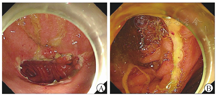

患者入院体格检查示体温为36.7 ℃,血压为110/75 mmHg(1 mmHg=0.133 kPa),脉率为85次/min,体重指数为14.3 kg/m2(身高为1.63 m,体重为38 kg),消瘦,慢性病容。双肺呼吸音较弱,腹韧,上腹部深压痛,无反跳痛、肌紧张。肝脾肋下未及,未及腹部包块。肠鸣音为2~3次/min。双下肢无水肿。血常规检查示白细胞计数为5.07×109/L,血红蛋白为108 g/L,血小板计数为309×109/L,粪便隐血试验阳性,肝、肾功能无异常,超敏C反应蛋白(hypersensitive C-reactive protein,hsCRP)为18.00 mg/L,红细胞沉降率为41 mm/1 h,铁蛋白为82 ng/mL,凝血功能无异常。结核菌素试验、结核感染特异性T细胞检测结果均呈阴性。外周血巨细胞病毒和EB病毒DNA、巨细胞病毒免疫球蛋白M、巨细胞病毒抗原血症检测结果均呈阴性。外周血需氧菌、厌氧菌、结核分枝杆菌、真菌培养和痰液病原学培养结果均呈阴性;胃黏膜活检组织结核分枝杆菌DNA检测(聚合酶链反应法)结果呈阴性。胸腔积液检验示白细胞计数为880×106/L,单核细胞占94.8%,ADA为60.2 U/L,结核感染特异性T细胞检测阳性[以每1×106个单个核细胞(mononuclear cell,MC)中斑点形成细胞(spot forming cell,SFC)的数目计,为64 SFC/(1×106MC)],细菌和真菌培养结果均呈阴性。抗核抗体谱、抗中性粒细胞胞质抗体、针刺试验结果均呈阴性。糖类抗原125为56.9 U/mL,胃泌素为127 pg/mL(未停用PPI),血清和尿免疫固定电泳检查均未见异常,在胸腔积液中未找到肿瘤细胞。腹盆部增强CT检查示胃体和胃底部黏膜面不规则伴黏膜面异常强化。2022年2月11日复查胃镜,于胃角见巨大溃疡,横贯胃角,延伸至幽门口,溃疡表面薄白苔,窦体交界前壁另可见2处长径为5~10 mm、与胃角溃疡外形特点相似的溃疡(图1);幽门螺杆菌快速尿素酶试验结果呈阴性;活检病理示胃黏膜中度慢性炎和轻度活动性炎,局部腺体增生,高倍视野下未见异常形态;免疫组织化学检查示巨细胞病毒阴性;特殊染色检查示抗酸染色未见抗酸杆菌,弱抗酸染色阴性;原位杂交技术检查示EB病毒编码的小RNA原位杂交(Epstein-Barr virus encoded small RNA-in situ hybridization,EBER-ISH)阴性。为除外淋巴瘤,2022年2月28日先后行超声内镜细针穿刺及胃镜下深挖和黏膜圈套活检,仍可见胃角、窦体交接前壁处巨大溃疡,溃疡形态、大小与2022年2月11日胃镜检查所见大致相同(图2);病理示(胃角)炎性渗出物和肉芽组织;免疫组织化学检查示CD10(部分阳性),Bcl-6阳性,CD2(T细胞)、CD3(T细胞)、CD20(B细胞)、CD4(T细胞)、CD5(T细胞)、CD7(T细胞)、CD8(T细胞)均阳性,Mum-1阳性,CD30(Ki-1)、CD56、巨细胞病毒均阴性,Ki-67指数为70%; EBER-ISH阴性。完善18F-氟代脱氧葡萄糖、正电子发射计算机断层显像检查见甲状腺左叶2个代谢增高的低密度结节,最大标准摄取值(maximum standard uptake value,SUVmax)为25.6;胃体大、小弯侧局部胃壁略增厚伴代谢增高(SUVmax为7.3);胃小弯侧、腹膜后多发代谢轻度增高淋巴结;右肺上叶代谢增高微结节,右肺中叶代谢增高结节、实变影(SUVmax为9.4)。甲状腺左叶代谢增高结节经超声穿刺活检确诊为甲状腺乳头状癌。

患者入院后反复上腹痛伴高热,最高体温为39.8 ℃,hsCRP升至114.53 mg/L,消耗症状明显,故置入空肠营养管进行鼻饲。为除外药物热停用抗结核药物3 d,患者最高体温未下降。2022年3月9日起反复呕血,血红蛋白最低为46 g/L,伴失血性休克,分别于3月10、12和23日行胃镜下止血治疗。提请病理科、呼吸内科、感染内科、风湿免疫科进行多学科讨论。关于胸腔积液,感染内科和呼吸内科考虑结核性胸膜炎诊断成立,但不能解释胃溃疡和患者全身表现,又因患者胃肠道耐受差,故于2022年3月11日起予抗结核药物静脉给药治疗,具体方案为异烟肼0.4 g/次、1次/d,左氧氟沙星0.5 g/次、1次/d,阿米卡星0.4 g/次、1次/d,利奈唑胺0.6 g/次、1次/d 。在胃溃疡治疗方面,因多次活检均无淋巴瘤和感染性疾病证据,而2021年10月9日外院胃镜活检见胃角小血管壁增厚、管腔狭窄,存在血管炎的表现,加之既往有自身免疫性角膜炎病史,风湿免疫科考虑胃溃疡为血管炎所致可能,不除外继发于结核感染。2022年3月11日起给予甲泼尼龙40 mg/次、1次/d静脉滴注,此后患者体温正常,腹痛缓解。2022年4月26日复查hsCRP降至15.00 mg/L,同日复查胃镜示胃角巨大溃疡较治疗前(2022年2月11日和28日)稍变浅;胃窦前壁、大弯、后壁侧仍可见散在溃疡(图3)。2022年4月28日将抗结核药物(异烟肼、利福平、左氧氟沙星、乙胺丁醇)调整为口服剂型。治疗1周后,患者再次出现发热(最高体温为39.2 ℃)、腹痛,hsCRP升至57.00 mg/L,血红蛋白由85 g/L降至62 g/L。患者在规范抗结核和抗血管炎治疗近2个月后疗效不理想,经消化内科、感染内科、风湿免疫科和基本外科多学科会诊,考虑有手术指征,遂于2022年5月10日行腹腔镜下远端胃次全切除+胃-空肠Roux-en-Y吻合术。术中见胃体部与腹壁致密粘连,该处胃壁组织菲薄,游离后见长径约为5 cm的胃壁缺损,符合慢性穿透性溃疡。手术标本高通量二代测序(next generation sequencing,NGS):巨细胞病毒种特异性序列数为19,相对丰度为63.4%。术后标本病理学检查示胃黏膜慢性炎,多灶淋巴细胞聚集,可见溃疡形成,部分穿透肌层,胃壁散在炎症细胞浸润,神经纤维增生,系膜及胃壁内小动脉内膜增厚,部分管腔狭窄,巨细胞病毒染色阳性(图4),病变不除外感染和缺血损伤;两侧断端未见特殊,淋巴结慢性炎;特殊染色检查示抗酸染色未见抗酸杆菌,弱抗酸染色阴性;原位杂交技术检查示EBER-ISH阴性。结合手术标本病原和病理学检查结果,修正诊断为巨细胞病毒胃炎。2022年5月13日起予更昔洛韦200 mg/次、1次/12 h静脉输注抗巨细胞病毒治疗。同时因胸腔积液明显改善,且抗结核治疗已满半年,停用抗结核药物。